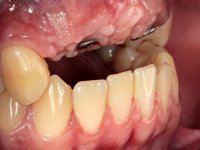

10 weeks after the surgery, a first impression was done to do a CAD-CAM provisional bridge (based on the diagnostic wax-up), that worked the soft tissue architecture during two months. This architecture was copied in a second impression by individualizing the impression copings in their emerging profile.

The working model was scanned and the dental technician developed a zirconia framework based on the diagnostic wax-up. This framework try-in was done, the perfect fit was assessed, and a final impression was done with a light silicone.

The bridge was finally placed with a progressive screwing to allow the tissue to accommodate the pressure of the pontics and the abutments emergency profiles.